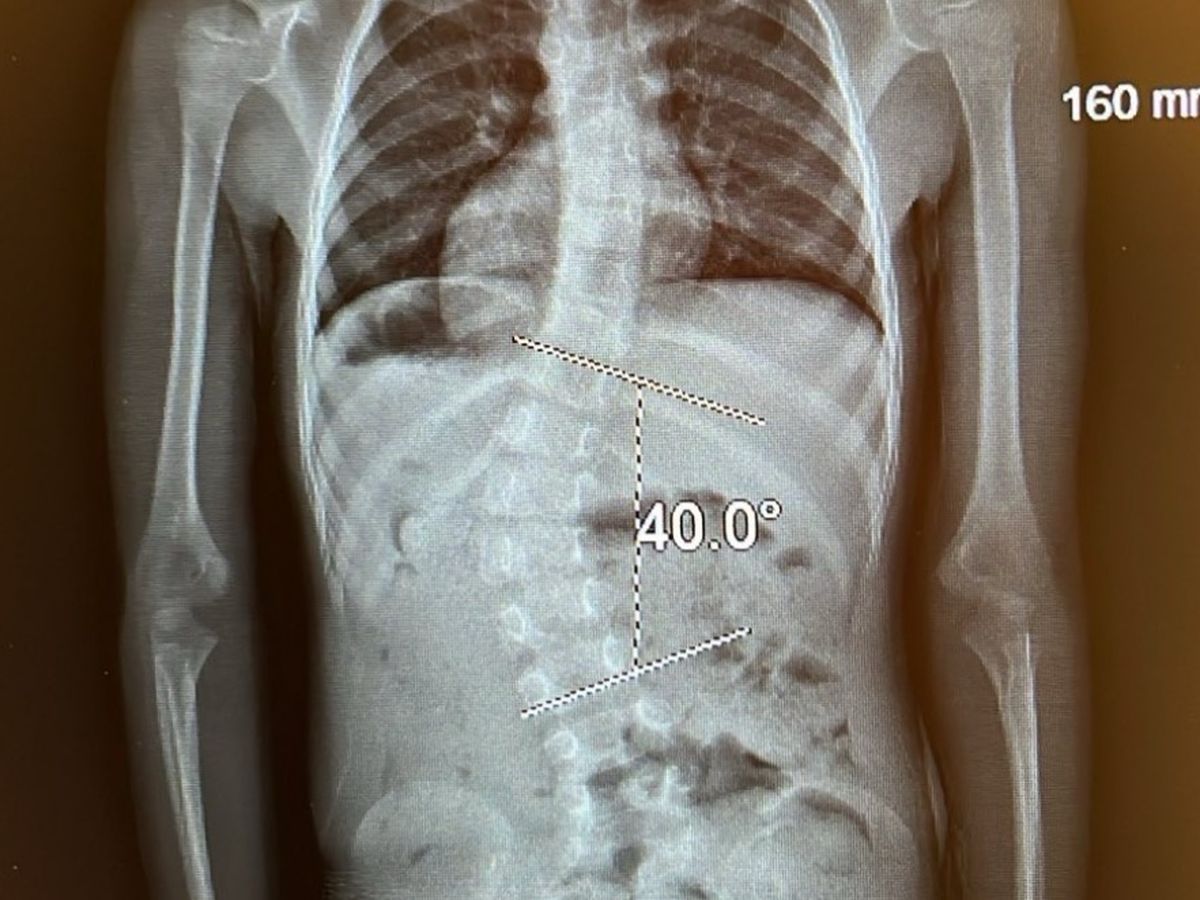

Our youngest gkid, Lenya, was born with scoliosis and has worn "body casts" off and on for the last three years! But what a courageous little missy and truth be known, she will likely ending up needing surgery when she gets older and her spine quits growing to some degree. However, my daughter, Kayla, holds the staff at Shriners in highest regard and so in honor of little missy's 6th birthday today, I have created a GoFundMe page to help the magnificent folks at Shriner's continue their mission. Thanks in advance for your contribution to this cause that means so much to us.